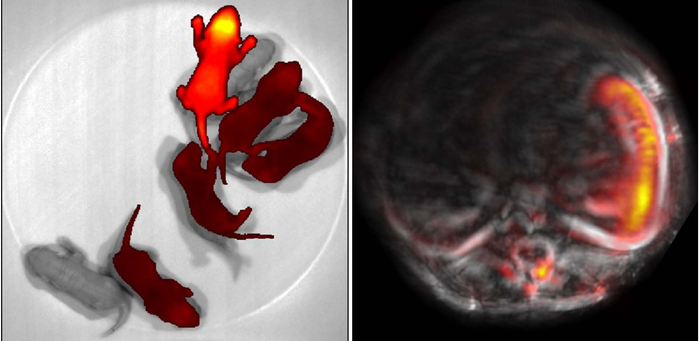

As a proof of concept, the team imaged the liver, stomach, spleen and intestine to show how different organs in the model expressed the photoreceptor. They saw that while all organs appeared more clearly than with standard PA, the spleen and liver were especially precise, as they had naturally higher levels of the biliverdin molecule for the BphP1 to bind to. This improved detail enabled the team to monitor changes, like liver regeneration, more precisely, and to track the efficacy of different protein delivery methods.

The new technique also allowed the team better study pregnancy in their mice, as BphP1 could bind directly to the embryos. The team was able to use PA to precisely identify seven embryos from the surrounding vasculature and maternal organs.